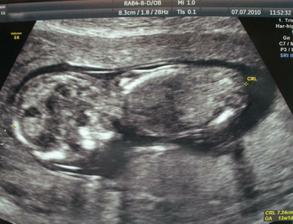

25. června 11+4tt - 4,8 cm, ubráno něco málo léků. 57,5kg

2. července 12+5tt - odběry k NT screeningu, vystaven průkaz pro těhotné - konečně!!!!!!! Termín porodu 8. ledna 2011. 58kg

7. července 13+3tt - NT screening - OK, termín porodu 9. ledna 2011.